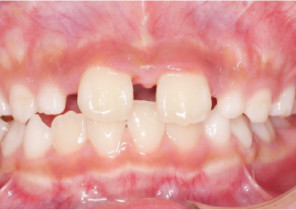

Pre Invisalign Palatal Expander Expansion

Post Invisalign Palatal Expander Expansion

After Invisalign First treatment

Case Report 1

10 years 0 months old, 18 stages of Invisalign Palatal Expanders

Courtesy of Dr. Sandra Khong Tai